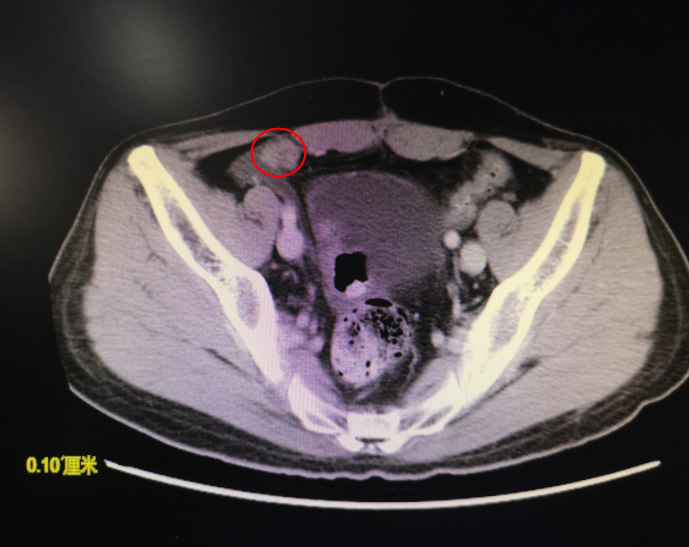

2009.03.11行CT检查提示:

盆腔右侧团状软组织密度影,大小12cm*5.8cm,考虑起源于腹膜后或是肠系膜恶性肿瘤。

2015.04.10我院复查CT提示:右下腹部新见结节影。